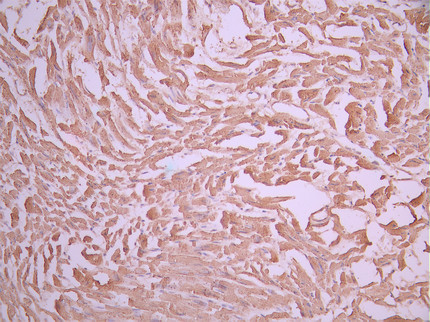

IHC image of CSB-RA623101MA1HU diluted at 1:50 and staining in paraffin-embedded human heart tissue performed on a Leica BondTM system. After dewaxing and hydration, antigen retrieval was mediated by high pressure in a citrate buffer (pH 6.0). Section was blocked with 10% normal goat serum 30min at RT. Then primary antibody (1% BSA) was incubated at 4°C overnight. The primary is detected by a Anti-Human lgG, Fcy Fragment Specific labeled by HRP and visualized using 0.05% DAB.